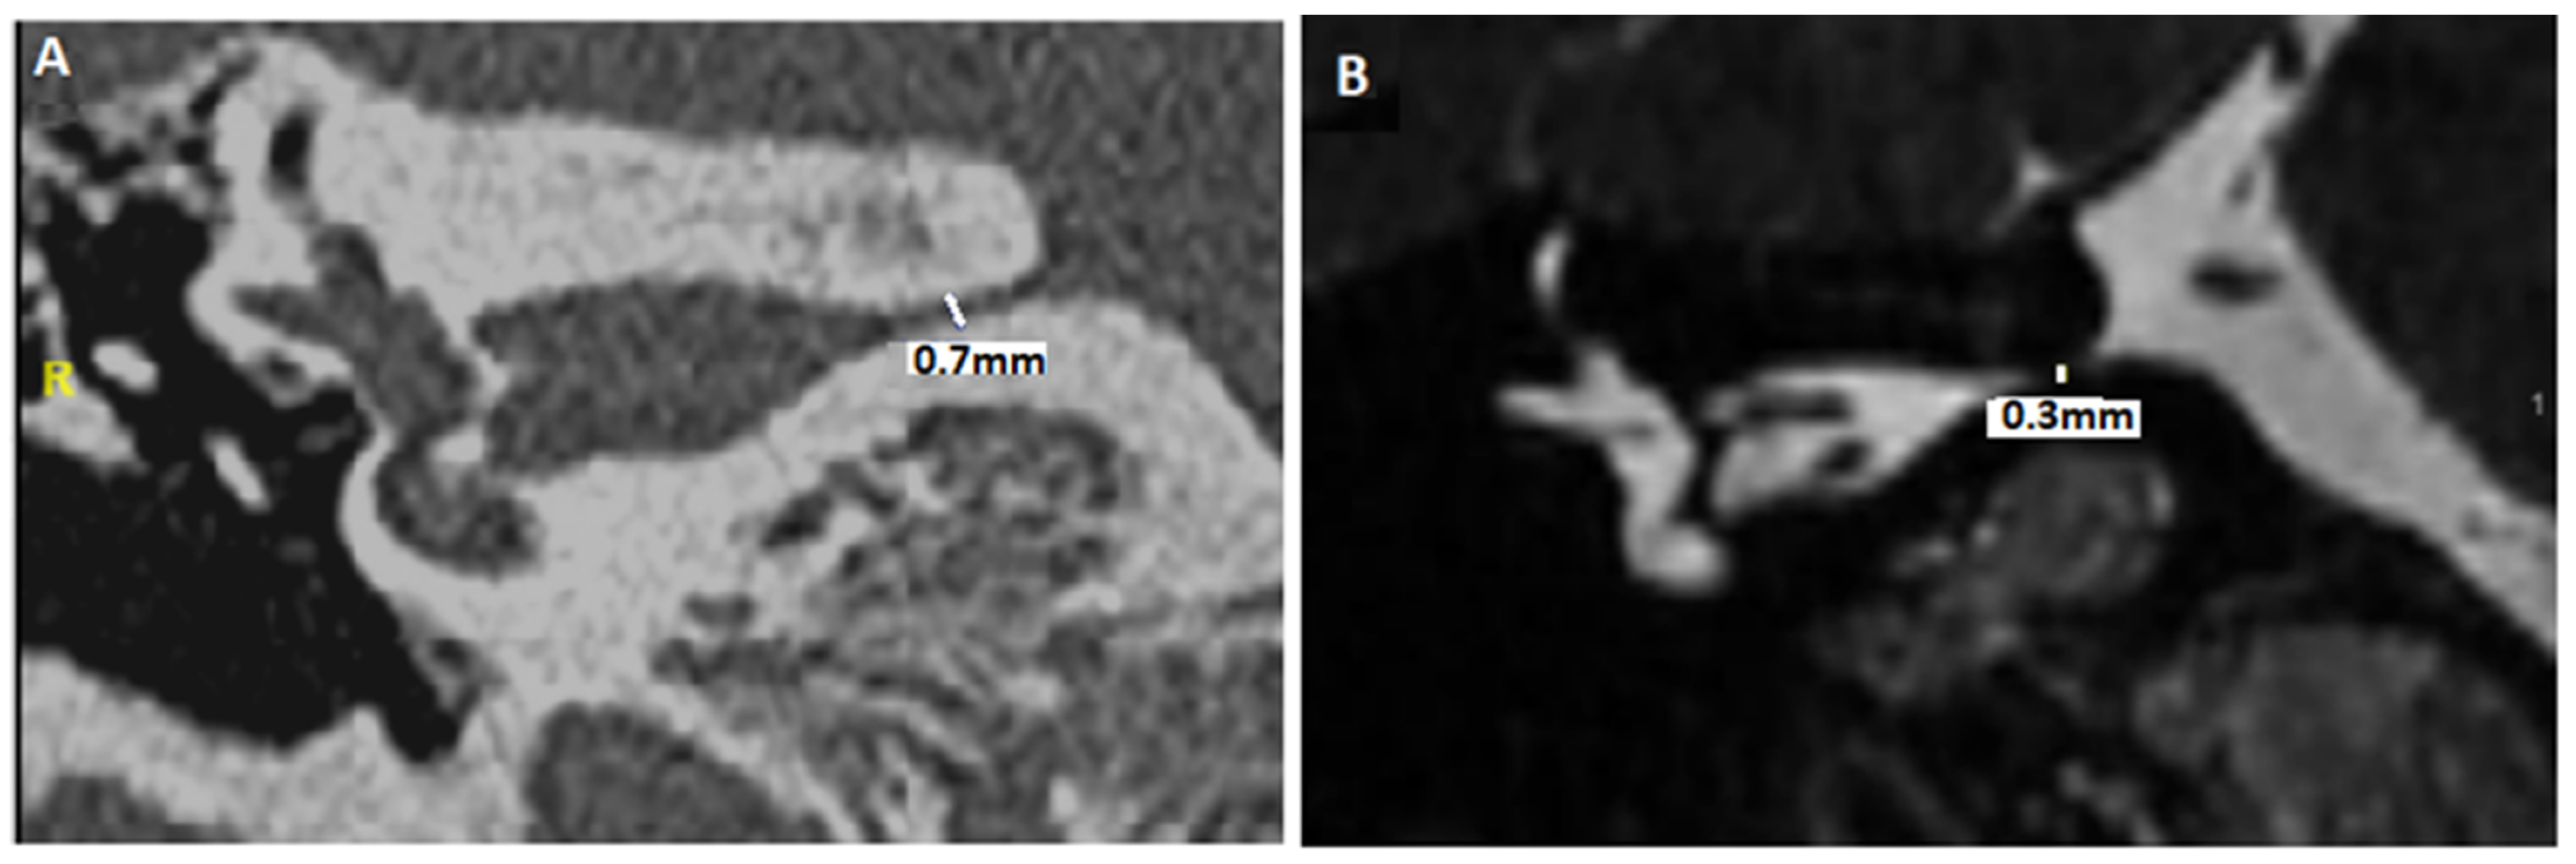

- Idriss, S.A.; Thai-Van, H.; Altaisan, R.; Ltaief-Boudrigua, A.; Reynard, P.; Ionescu, E.C. The Narrowed Internal Auditory Canal: A Distinct Etiology of Pediatric Vestibular Paroxysmia. J. Clin. Med. 2022, 11, 4300. [Google Scholar] [CrossRef]

- Ionescu, E.C.; Reynard, P.; Idriss, S.A.; Ltaief-Boudriga, A.; Joly, C.A.; Thai-Van, H. The “Near”-Narrowed Internal Auditory Canal Syndrome in Adults: Clinical Aspects, Audio-Vestibular Findings, and Radiological Criteria for Diagnosis. J. Clin. Med. 2023, 12, 7580. [Google Scholar] [CrossRef]

- Valvassori, G.E. The internal auditory canal revisited. The high-definition approach. Otolaryngol. Clin. N. Am. 1995, 28, 431–451. [Google Scholar] [CrossRef]

| HRCT Diagnosis Steps | MRI Diagnosis Steps |

|---|---|

| - Evaluation of the smallest anteroposterior and craniocaudal IAC diameters (after measuring IAC length) - Description of bony abnormalities of the IAC walls (normal bone, fibrous dysplasia, meningeal calcifications, and/or osteoma of exostosis) - Evaluation of any significant angulation or deformation of the IAC (anteroposterior and craniocaudal planes) | - Assessment of the perineural fluid environment in the IAC - Angulation of the CVN? - Presence of NVCC? - Analysis of fusion images between high-resolution T2 and HRCT of the temporal bones - Evaluation of anteroposterior and craniocaudal diameters of the IAC |